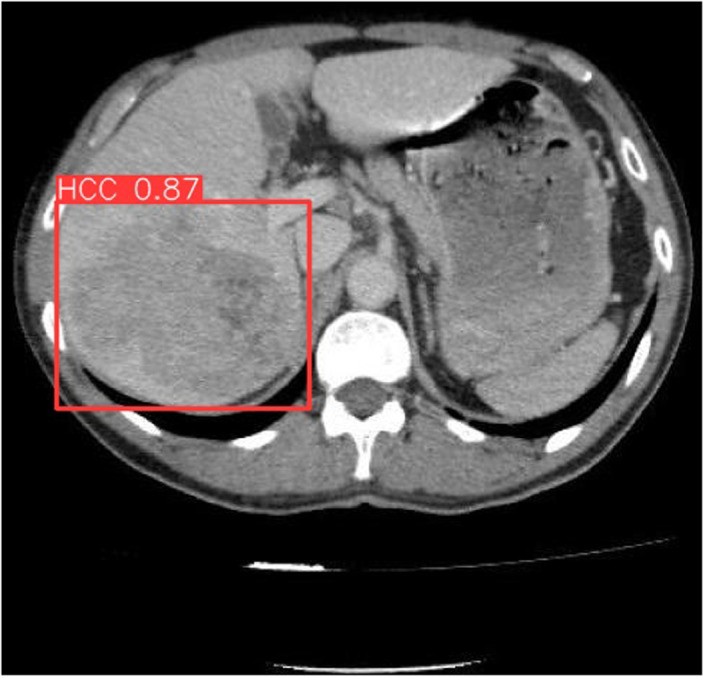

Hepatocellular carcinoma (HCC) is a prevalent cancer that significantly contributes to mortality globally, primarily due to its late diagnosis. Early detection is crucial yet challenging. This study leverages the potential of deep learning (DL) technologies, employing the You Only Look Once (YOLO) architecture, to enhance the detection of HCC in computed tomography (CT) images, aiming to improve early diagnosis and thereby patient outcomes. We used a dataset of 1290 CT images from 122 patients, segmented according to a standard 70:20:10 split for training, validation, and testing phases. The YOLO-based DL model was trained on these images, with subsequent phases for validation and testing to assess the model's diagnostic capabilities comprehensively. The model exhibited exceptional diagnostic accuracy, with a precision of 0.97216, recall of 0.919, and an overall accuracy of 95.35%, significantly surpassing traditional diagnostic approaches. It achieved a specificity of 95.83% and a sensitivity of 94.74%, evidencing its effectiveness in clinical settings and its potential to reduce the rate of missed diagnoses and unnecessary interventions. The implementation of the YOLO architecture for detecting HCC in CT scans has shown substantial promise, indicating that DL models could soon become a standard tool in oncological diagnostics. As artificial intelligence technology continues to evolve, its integration into healthcare systems is expected to advance the accuracy and efficiency of diagnostics in oncology, enhancing early detection and treatment strategies and potentially improving patient survival rates.